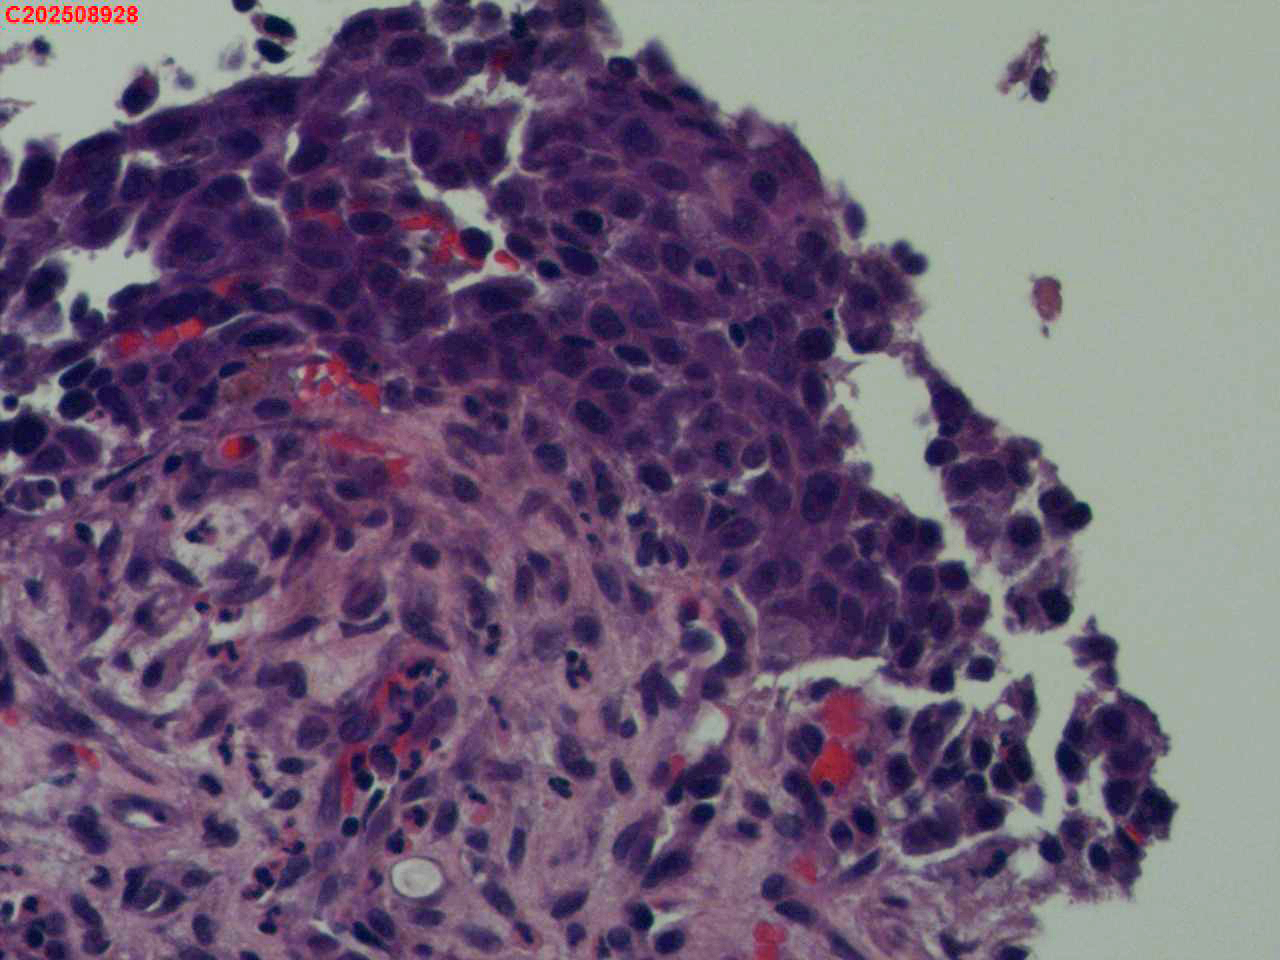

喉部右侧、声带下方咬检

喉室内右侧声带下方新生物。

考虑鳞癌

鳞癌,有微浸润